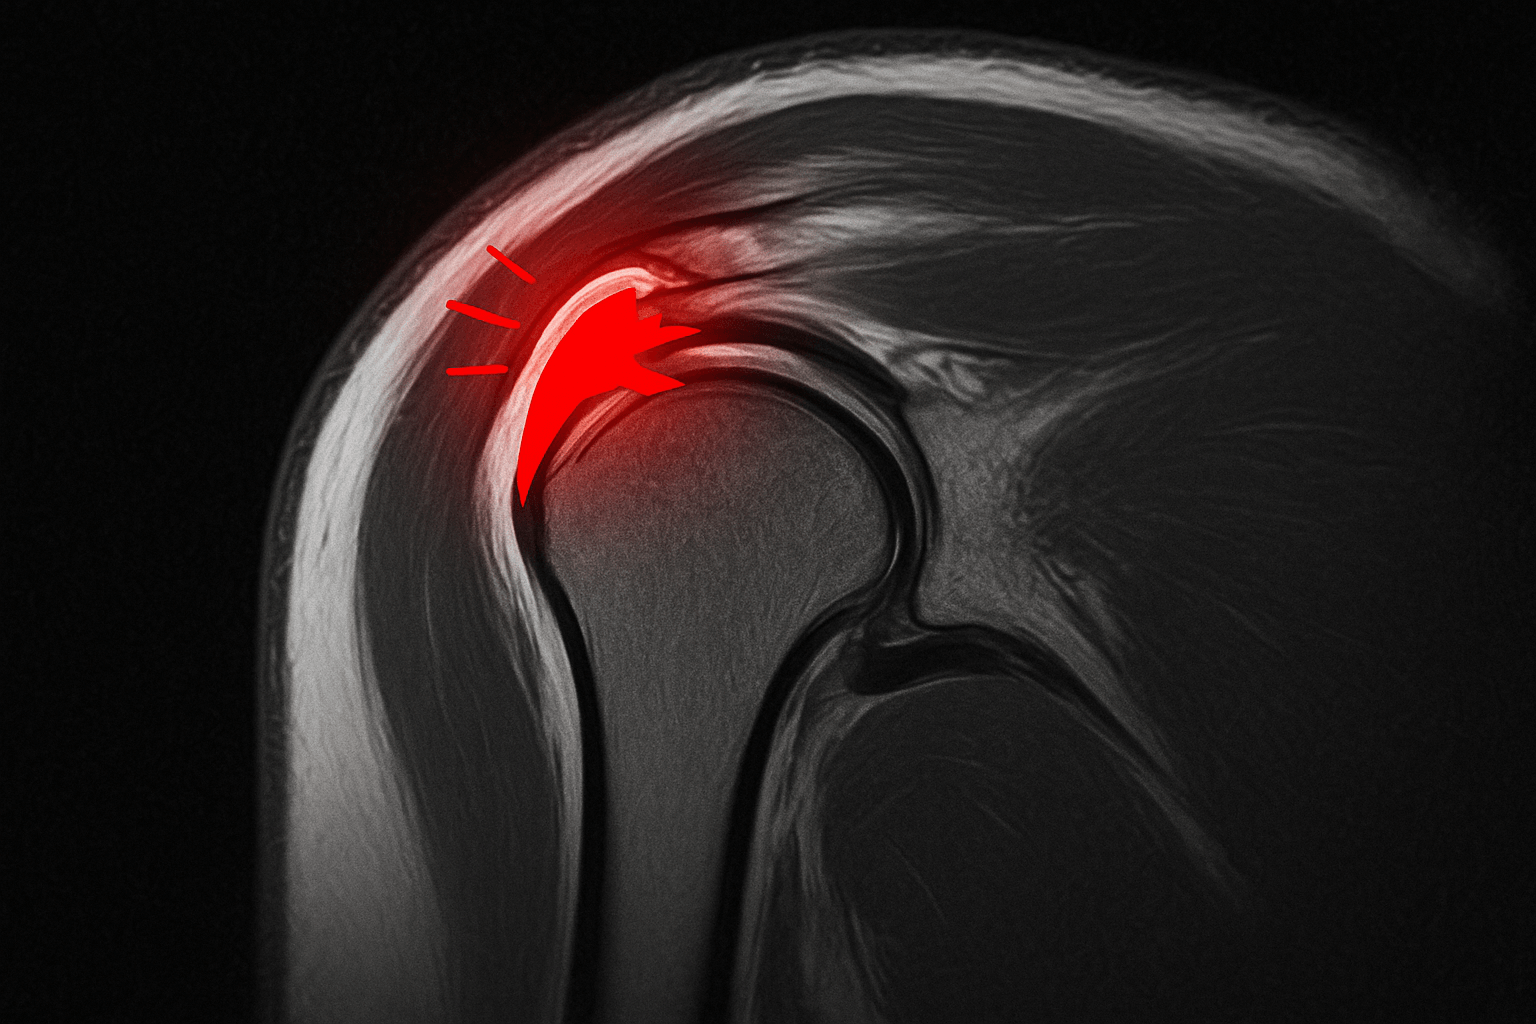

회전근개 파열, 무엇인가요? 🤔

회전근개는 어깨 관절을 안정적으로 유지하고 팔을 움직이는 데 필수적인 네 개의 힘줄(극상근, 극하근, 견갑하근, 소원근)과 그 주변 근육을 통칭하는 말입니다. 이 중요한 힘줄들이 부분적으로 손상되거나 완전히 끊어지는 상태를 회전근개 파열이라고 합니다. 주로 노화로 인한 퇴행성 변화, 반복적인 어깨 사용, 스포츠 활동 중 발생하는 외상 등이 원인이 되며, 최근에는 젊은 층에서도 발병률이 증가하는 추세입니다.

완전(전층) 파열이거나 파열 범위가 매우 큰 경우, 또는 보존적 치료에도 불구하고 증상 호전이 없는 경우에 고려됩니다.

- 관절내시경 봉합술: 1cm 이하의 작은 절개로 관절내시경을 삽입하여 파열된 힘줄을 정교하게 봉합하는 방법입니다. 기존 개방형 수술에 비해 회복이 빠르고 흉터가 적다는 장점이 있습니다.

- PRP(자가혈 성장인자) 주사 병합: 수술 중 환자의 혈액에서 추출한 농축된 혈소판(PRP)을 손상 부위에 주입하여 힘줄 재생을 촉진하고 재파열 위험을 낮추는 데 도움을 줍니다.